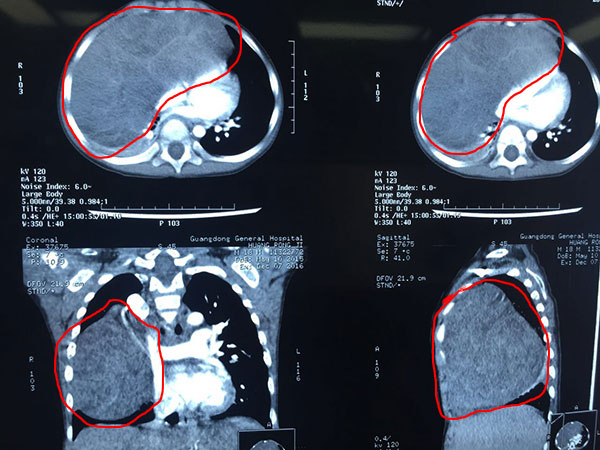

带着最后的希望,小吉父母慕名来到省医肺研所。科室接诊之后高度重视,立刻将孩子转至PICU密切监护。时间就是生命,肺研所立刻启动了全院会诊,邀请小儿心外,胸外科,麻醉科,PICU、影像科,相关专家组成治疗小组,制定全面细致的手术治疗计划。术前检查结果显示,孩子胸腔右前中纵隔肿块大小约74mm×130mm,几乎一个香瓜的大小。术前穿刺活检病理明确病理为全面的手术计划做好预案。肺科、心儿科和胸外科的主刀专家根据影像科提供的影像材料明确了肿瘤的供养血管,及受压迫后重要脏器心肺等及上腔静脉、主动脉的毗邻位置,详细谈论了手术步骤和应急方案。麻醉科、PICU也做好肿瘤娩出后复张性肺水肿等预处理,以防术后呼吸衰竭。

术前影像显示肿瘤非常大

半年前的小吉,一次着凉感冒后出现了咳喘、气促症状,而且程度日益加重。爱子心切的小吉父母携子到医院查验,没想到CT结果显示,孩子小小的胸腔里竟有个肿瘤,而且肿瘤体积巨大!不仅占据两侧胸腔,并且挤压心肺,甚至被挤压的右肺在CT片上几乎已经看不到了!尽快手术摘除肿物、解除对心肺的压迫是唯一出路,否则,随着肿瘤日益增大,心肺长期压迫受损,孩子将最终呼吸衰竭而亡。闻此噩耗,小吉父母心如刀绞,急切请当地医院马上进行治疗。可由于孩子年龄太小、肿物过于巨大,而且所处位置包围着许多重要血管结构,手术风险太高,当地医院婉言拒绝,建议到其他医院试试。